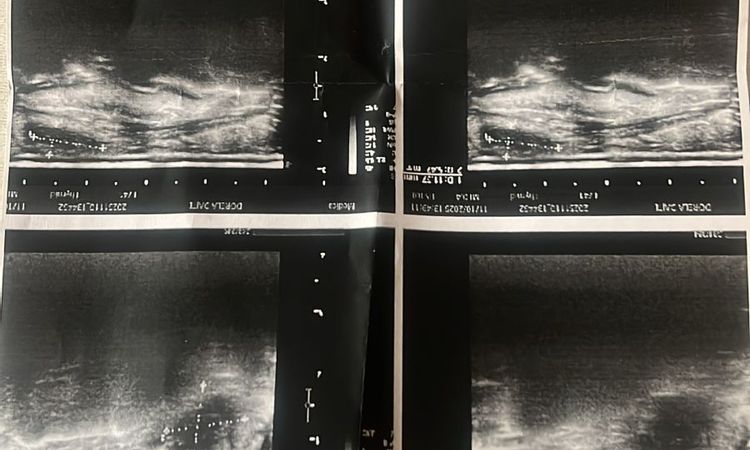

Buongiorno. Le ho già risposto ma le rimando la mia opinione . Un granuloma è dovuto a una infezione . Dall ‘ ecografia sembra più formazione cistica attorno ad un corpo estraneo. Purtroppo sul mercato stanno diffondendosi prodotti perfettamenti contraffatti difficilmente riconoscibili dagli stessi medici da quelli autentici di ottima qualità’. Si rivolga a medici sicuri e si informi bene sui prodotti e la loro provenienza. Arrivano spesso tramite Internet. Personalmente li compro direttamente nella stessa farmacia che vende solo a medici. E sono prodotti più cari ma sicuri e di maggior durata.